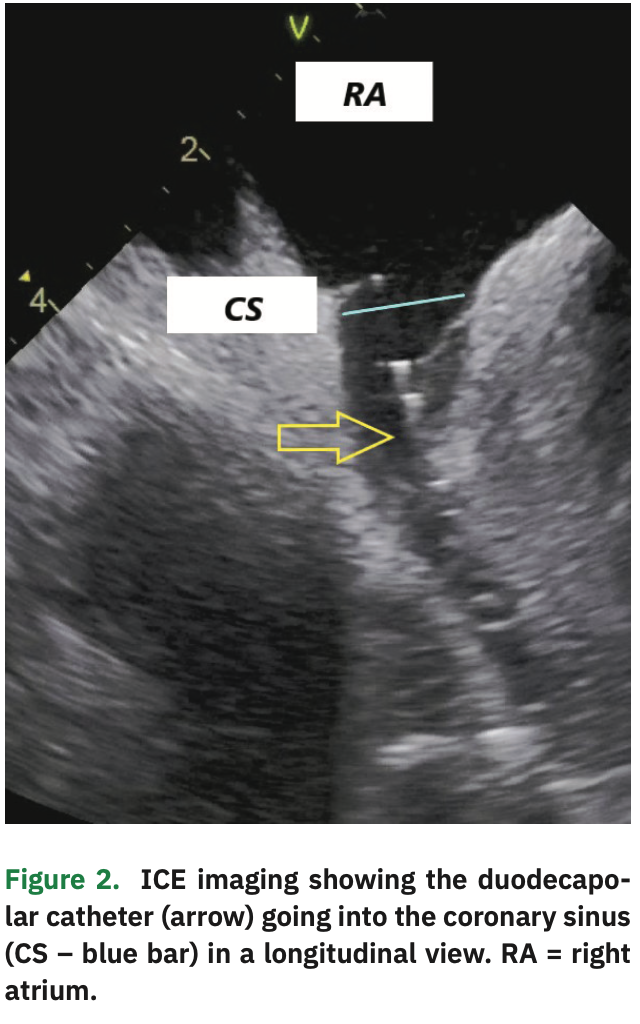

An irrigated 3.5 mm ablation catheter with contact force sensor was advanced under EA visualization and a limited right atrial map constructed, mostly to create a matrix (allowing other catheters to be visualized in EA maps) and to delineate the septum and CS anatomy. The CS was cannulated with the duodecapolar catheter under EA and ICE visualization (Figure 2). The distal 10 poles were in the CS, with the proximal poles in the RA.